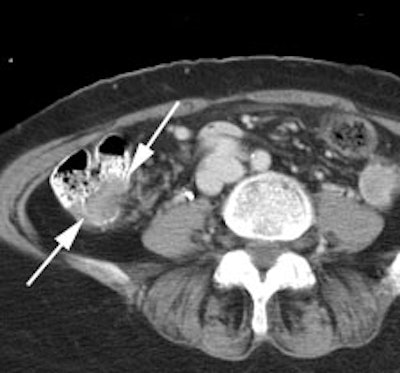

Bladder cancer: Dilute urinary activity in this patient's bladder allowed accurate detection of their bladder cancer (white arrows on CT, black arrows on PET scan). In general, urinary excretion of FDG limits evaluation of urinary tract malignancies, however, hydration and diuresis can improve diagnostic accuracy. |

|